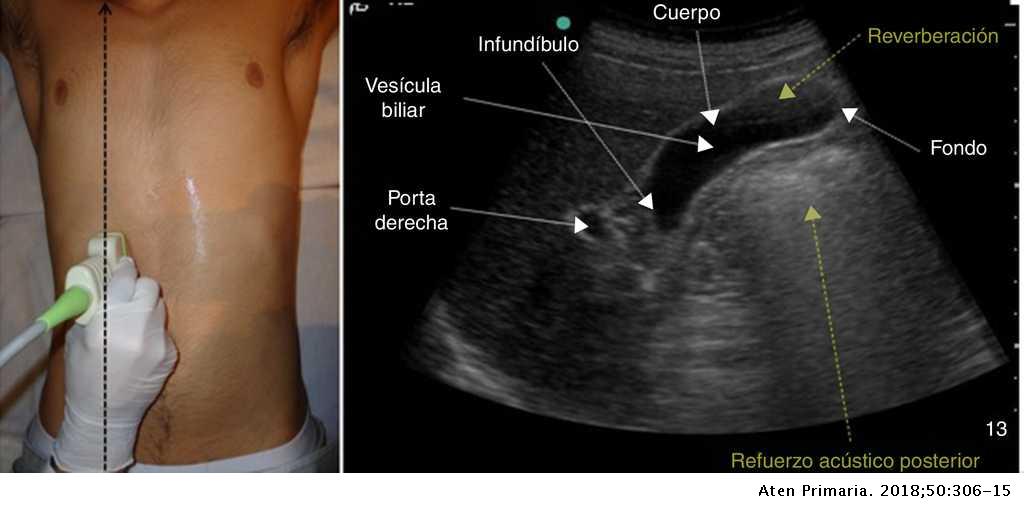

Dr Raúl Vargas Ultrasonido Abdomen Completo YouTube

Ultrasonido abdominal en el que se aprecia dilatación del conducto

Dr Raúl Vargas Ultrasonido Abdominal Completo YouTube

Imagenes de ultrasonido abdominal general YouTube